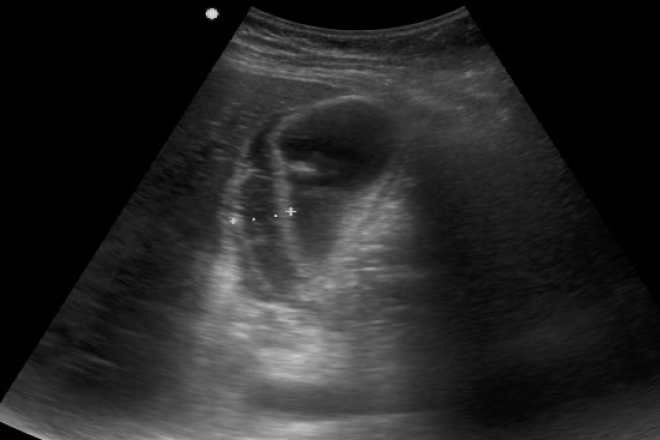

El ultrasonido es el principal procedimiento de imagen para demostrar la existencia de cálculos. Esta técnica no invasiva es eficaz y es independiente de la función hepática. Además de demostrar la vesícula biliar, el ultrasonido proporciona información adicional importante al poner de manifiesto el árbol biliar y el parénquima hepático.

El diagnóstico por Ultrasonido de la litiasis biliar se basa en 3 criterios: 1) Los cálculos aparecen en el ultrasonido como imágenes ecogénicas. Los cálculos muy pequeños pueden no dejar sombra acústica. Para detectarlos, hay que usar el transductor de la máxima frecuencia posible que permita visualizar la vesícula biliar. Además, la ganancia debe ser la mínima posible para no enmascarar una sutil sombra acústica, 2) asociados a sombra acústica y 3) la movilidad de los cálculos libres flotantes se puede demostrar moviendo al paciente permitiendo con ello una mayor caracterización ultrasonográfica. La movilidad se comprueba cambiando al paciente de la posición de supino a la de decúbito lateral izquierdo.

La colecistitis aguda litiásica es una inflamación aguda de la vesícula biliar desencadenada en el 90% de los casos por la obstrucción de la vesícula o del conducto cístico por un cálculo. Los cálculos son el principal factor etiológico y su detección es un requisito.